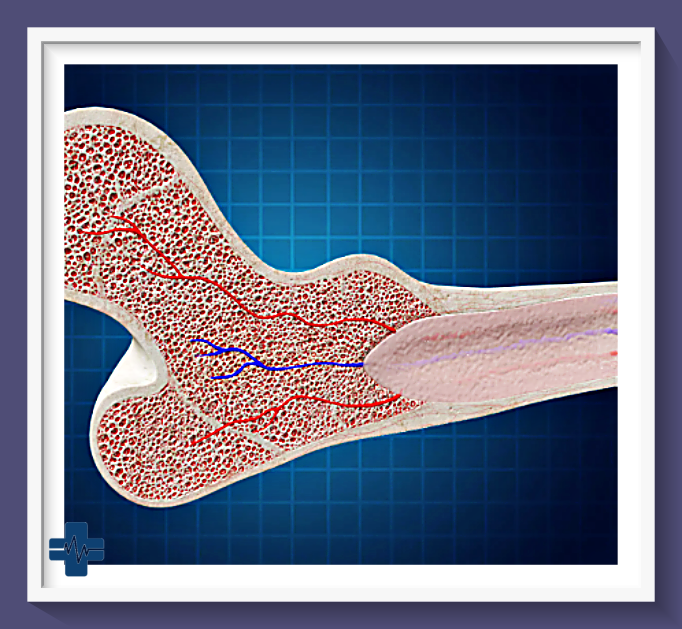

골수암, 특히 급성 및 만성 골수성 백혈병은 혈액암의 한 유형으로, 골수에서 비정상적인 백혈구가 과도하게 생산되는 질환입니다. 이 질환은 골수의 정상적인 기능을 방해하여 다양한 신체적 증상을 유발하며, 진단과 치료가 시급한 중대한 건강 문제입니다.

2. 조혈모세포 이식: 이는 손상된 골수를 건강한 골수로 대체하기 위한 치료법입니다. 환자의 골수를 파괴한 후 건강한 기증자의 조혈모세포를 환자에게 이식합니다. 이 방법은 완치를 목표로 하며, 특히 젊은 환자와 건강한 환자에게 권장됩니다.